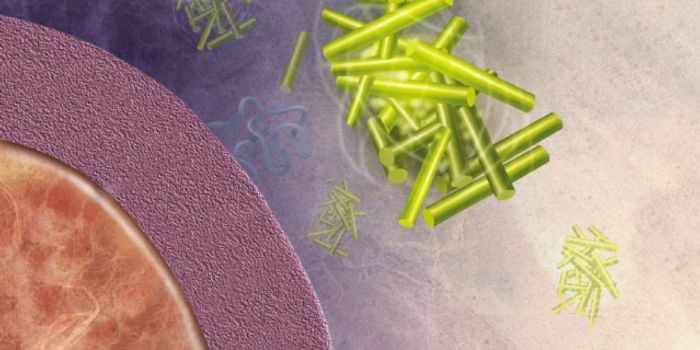

SEP 27, 2015NeuroscienceAmyloids, fibrous protein clumps often associated with diseases such as Alzheimer’s disease, form characteristic p ...